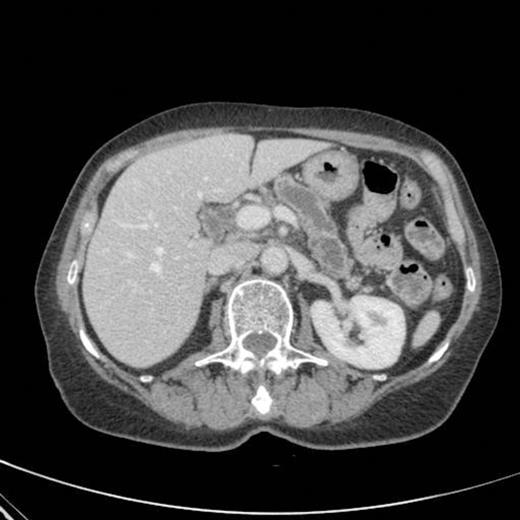

CT scan showing marked dilatation and tortuosity of the main pancreatic duct (12-13mm at the head) with atrophy of the body and tail

CT scan done 2 years later revealed marked dilatation and tortuosity of the main pancreatic duct (12-13mm at the head) with atrophy of the body and tail (Fig1). Repeat scans done on an yearly basis over the next three years reported no progressive change. CT scan done 6 years after the original diagnosis revealed pancreatic duct dilatation to 15 mm with side branch dilatation in uncinate process and atrophic pancreas (Fig 2). A diagnosis of mucinous ductal ectasia or an intraductal papillary mucinous tumour was suggested. On clinical review, patient complained of epigastric discomfort, loose stools, anorexia and weight loss. Upper GI endoscopy and colonoscopy was normal. Faecal elastase was less than 100 confirming pancreatic insufficiency for which she was commenced on creon.